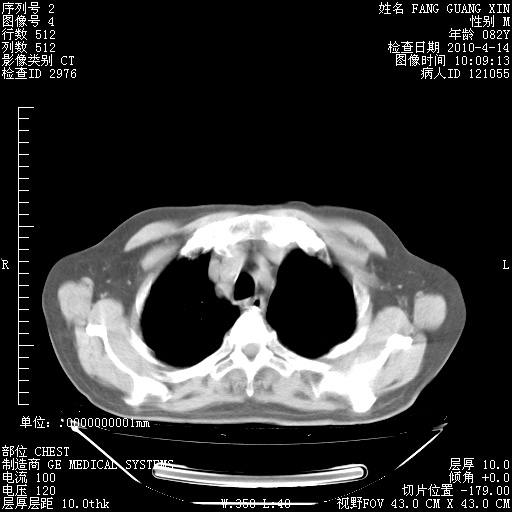

4月14日肺部CT

楼主| 发表于 2010-4-28 16:51 | 显示全部楼层

楼主| 发表于 2010-4-28 16:53 | 显示全部楼层

肺部CT平扫未见异常。